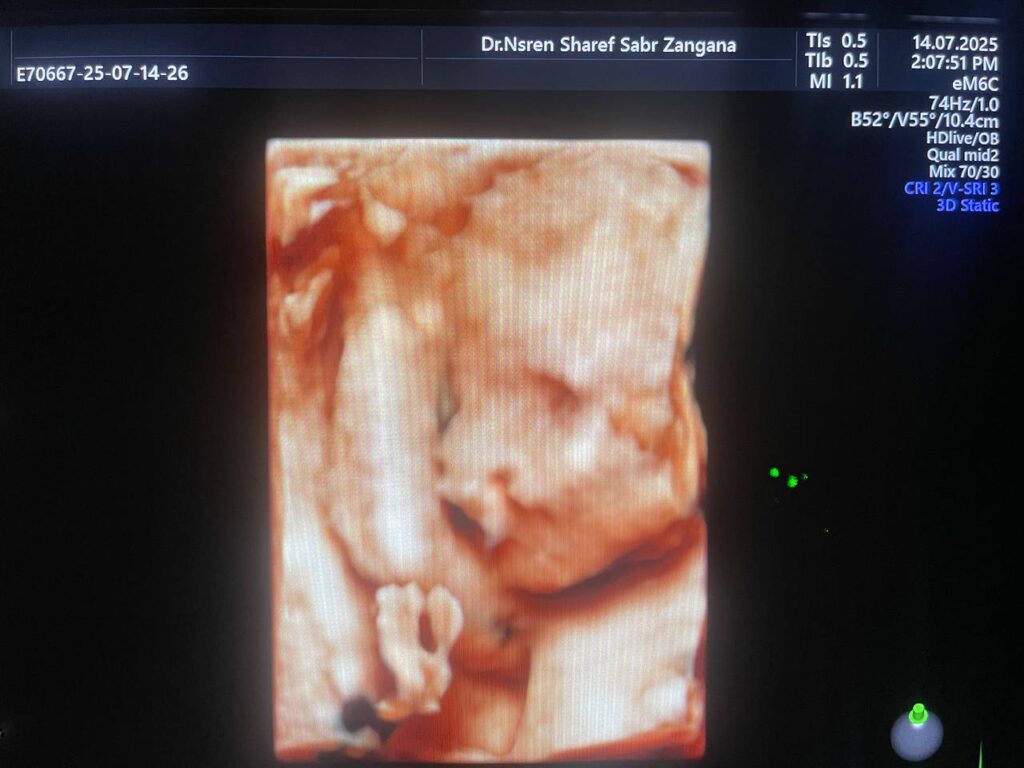

Multiple Craniofacial anomaly seen , mild dilated posterior atrium of the lateral ventricle 10.3mm , agenesis of the corpus callosum ??can not be excldued , bilateral cleft lip & palate , small orbits & hand anomaly , congenital heart disease can not be excldued , please for further study & echocardiography , Patau Syndrome? (Trisomy 13 ? ) can not be excldued ? please further study , no other anomaly can be detected now